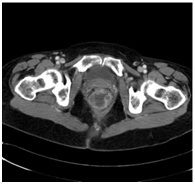

We describe the case of a 59 years old woman affected by rectal cancer which was diagnosed in April 2016 and involved the rectum from the anal margin for an extension of 7 cm and extended into the mesorectal lymphonodes withouth metastes (Figure 1). The patient underwent radiation and chemotherapy to reduce cancer mass. After 6 months, though, a full body CT scan showed a reduction of cancer mass into the rectum (which measured 2,5 cm from the anal margin with no lymphatic involvement) but multiple hepatic metastases were detected. The patient was not proposed for surgery due to the hepatic involvement and was given another chemotherapy cycle comprising cisplatin and fluorouracil. The patient complained of severe pain located in the perianal and perineal region, which was exacerbated by defecation. Basal Numerical Rating Score (NRS) for pain was 8 out of 10 and during defecation the patient reported a NRS of 10. Pharmacological treatment with dexamethasone, transdermal fentanyl and paracetamol didn’t give the patient substantial improvement. The patient was admitted to Palliative Care Department where Pregabalin was added and Fentanyl was replaced with subcutaneous Morphine 100mg/day. Even with this therapy the patient was still complaining for severe pain located in the perianal region. Rectal exploration was impossible for the extreme pain elicited in the patient by this manouver. After a consultation with the patient’s caregiver and the palliative care staff we decided to propose the patient for ganglion impar Radiofrequency (RF) ablation. Written consent was obtained from the patient. The procedure was performed under sterile conditions with fluoroscopic guidance. Antibiotic prophylaxis with intravenous cefazolin 2 g was given. The patient was prone positioned with a pillow under the iliac crests to reduce lumbar lordosis. Skin was anesthetized with 2% Lidocaine and a 18G 100 mm long RF needle with an active tip of 5 mm was inserted under fluoroscopic lateral vision at the sacro-coccygeal junction and the needle tip was positioned under the sacro-coccygeal ligament. Contrast (iopamidol 300) was injected and no vascular or epidural absorption was noticed, the contrast spread between the coccyx and the rectum outlining the ganglion impar (Figure 2) Sensory stimulation at 50 Hz was performed and the patient reported paraesthesia in the perianal region at 0.4 A intensity.

Figure 2 Fluoroscopic lateral vision showing needle positioning at the sacrococcygeal junction and the spread of contrast.